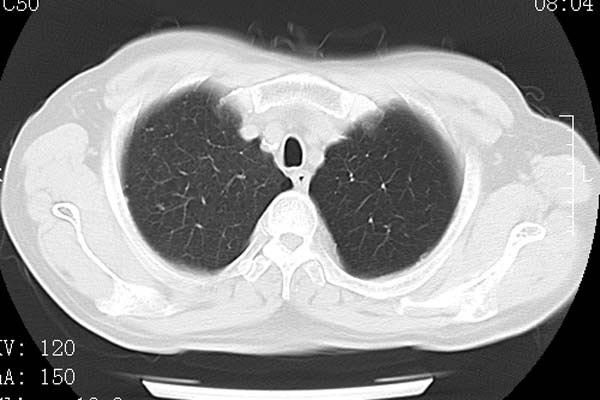

以下是引用守望可可西里在2008-6-24 1:11:00的发言:[br][br] 考虑为周围型肺癌:[br] 1.分叶结节,形态极不规则,蟹足样伸展的恶性浸润特征比较明确。[br] 2.磨玻璃影中由多个更高密度小结节聚集呈梅花瓣样。[br] 3.局部胸膜凹陷征比较明确。[br][br] 另:纵隔胸膜明显增厚、粘连。

以下是引用zjzjr在2008-6-24 11:19:00的发言:[br]支持左下肺周围型肺癌伴右肺转移,纵隔淋巴结转移,心包积液.

以下是引用zhangling在2008-6-24 14:56:00的发言:[br]我们科室意见报告为[br][br]1考虑左下肺周围型肺癌[br]2右肺小结节考虑转移瘤,纵隔淋巴结转移[br]3心包积液. [br] 各位老师分析的相当好 谢意[br]